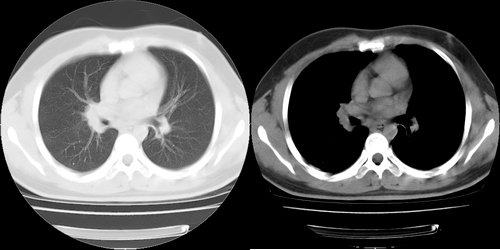

患者 男性 25岁,体检觉得右肺门感觉增大,请会诊,有没有异常?(我科诊断:未见异常)

右肺门增大,囊状影与肺动脉分支有关,上叶支气管受压移位。

考虑发生于右肺动脉分支的肺动脉瘤。

右主支气管及右中叶支气管受压,腔静脉后淋巴结肿大,不知肿块是血管还是淋巴s

建议增强

考虑为血管影 建议增强

建议增强,右肺上叶前段支气管受压变细,腔静脉后方见肿大淋巴结.考虑结节病或肺门占位.